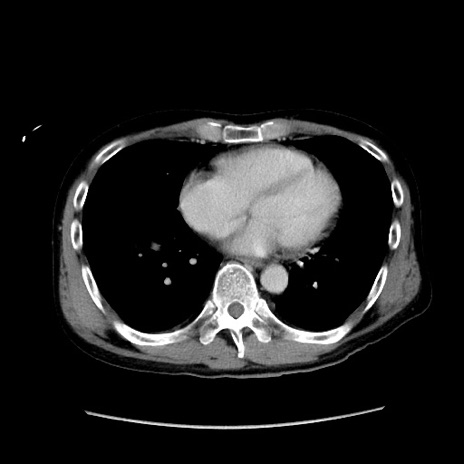

症例37(横断像)

【症例】40歳代 男性

【主訴】腹痛

【現病歴】4時間ほど前に電車に乗車中に臍部上より腹痛出現。徐々に増悪し起立困難となり、救急外来受診。生ものは数日食べていない。今朝お雑煮を食べた。

【身体所見】BT 36.8℃、BP 117/84mmHg、HR 91/min、SpO2 97%、苦悶様、腹部:臍上部広範囲圧痛あり、反跳痛±

【データ】WBC 8100、CRP 0.03